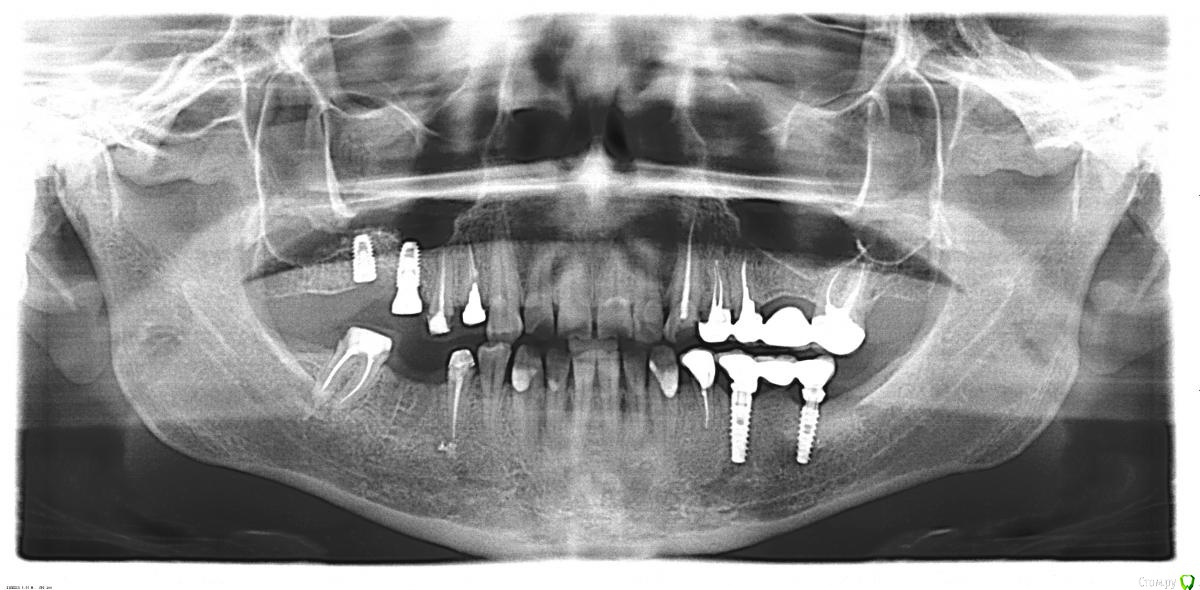

Петр Бриньковский Опубликовано 16 мая, 2016 Поделиться Опубликовано 16 мая, 2016 Пациентка уезжает через месяц далеко, просит отремонтировать весь рот. Снизу слева- импланты установлены 7 лет назад( производителя не знает)- сколы керамики, сверху справа импланты установлены в декабре прошлого года(судя по всему альфа-био), причем один с формирователем. Места для конструкций нет-завышение прикуса, жевательную часть хочет сделать металлокерамику, фронт -виниры Емах. Подскажите советом коллеги, у кого какие мнения по этому поводу Ссылка на комментарий

АнтонТЛТ Опубликовано 16 мая, 2016 Поделиться Опубликовано 16 мая, 2016 (изменено) Это не альфа, это что-то с конусным соединением Изменено 16 мая, 2016 пользователем АнтонТЛТ Ссылка на комментарий

kriokov Опубликовано 16 мая, 2016 Поделиться Опубликовано 16 мая, 2016 Это не альфа, это что-то с конусным соединением+100, верх- или имплантиум или импро ( из этой оперы, по соединению и фдм похоже) Ссылка на комментарий

Петр Бриньковский Опубликовано 17 мая, 2016 Автор Поделиться Опубликовано 17 мая, 2016 Верх-Osstem,низ- Mis. Подскажите кто работает на этих системах что необходимо купить для завершения работы(формировали, винты, ключи), абатменты думаю индивидуальные сделать. Ссылка на комментарий